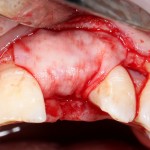

Затем укладывается и конфигурируется аутокостная стружка:

Если после этого BioGide намочить физраствором, им легко укрыть получившийся объем:

Для надежности можно зафиксировать пинами: